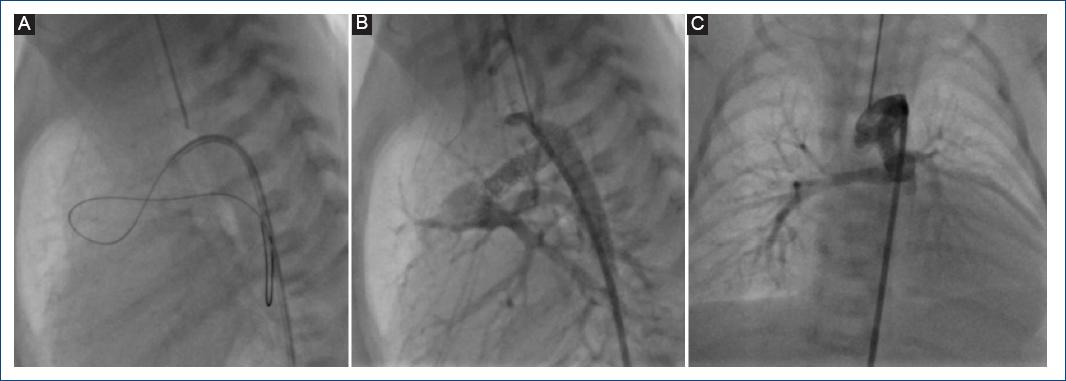

Figura 4 A: se logra deshacer el asa del conducto arterioso, rectificándolo con una guía de angioplastia coronaria de 0.014 pulgadas. B: proyección lateral izquierda que muestra una adecuada colocación del stent coronario no medicado, cubriendo toda la longitud del conducto. C: en proyección frontal se observa la rectificación del conducto con el stent coronario.

Dadas las ventajas del StD demostradas en este y otros estudios previos, vale la pena comentar que existen recomendaciones en relación al tipo de CA candidato a la colocación de StD. Se ha mencionado que los CA muy tortuosos (tipo 3) no son candidatos a la colocación de StD, pero en la mayoría de nuestros casos (excepto en dos) fue posible colocarlo de manera exitosa independientemente de la anatomía ductal, incluso en aquellos con un CA tipo 3, como se muestra en las figuras 3 y 4.